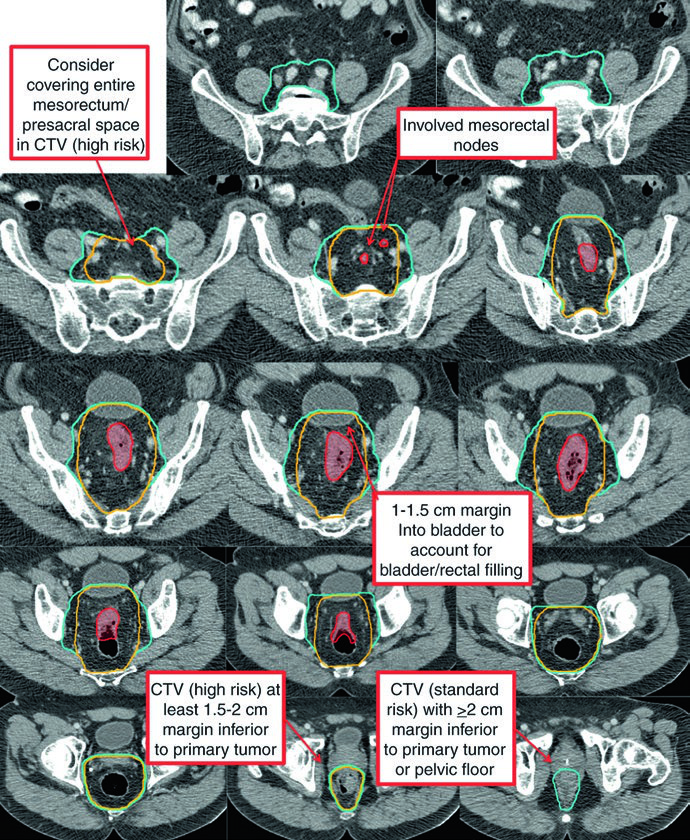

O CTV de alto risco (CTV-HR) deve incluir o GTV com margem mínima de 1,5 a 2 cm superior e inferiormente, além de todo o reto, mesorreto e espaço pré-sacral. Para linfonodos ilíacos externos ou inguinais macroscopicamente comprometidos, a margem GTV-para-CTV deve ser de no mínimo 10 a 15 mm. Em tumores T4, adiciona-se margem de 1 a 2 cm nos órgãos adjacentes invadidos (bexiga, próstata, cérvix).

O CTV de risco padrão (CTV-SR) cobre o CTV-HR completo, todo o mesorreto e os linfonodos ilíacos internos bilaterais. A inclusão dos linfonodos ilíacos externos e obturadores bilaterais é obrigatória para tumores T4 com envolvimento de órgãos anteriores (bexiga, cérvix, próstata). Se o tumor primário se estende inferiormente para o canal anal, os linfonodos ilíacos externos e inguinais bilaterais devem ser incorporados ao CTV-SR.

| CTV-HR | GTV-P e GTV-N com margem de 1,5-2 cm superior e inferiormente, excluindo osso, músculo e ar não envolvidos. Margem mínima de 10-15 mm para linfonodos ilíacos externos ou inguinais macroscópicos. Inclusão de reto, mesorreto e espaço pré-sacral no plano axial. Margem de 1-2 cm em órgãos adjacentes para T4 |

| CTV-SR | CTV-HR + mesorreto completo + linfonodos ilíacos internos bilaterais. Ilíacos externos e obturadores para T4 com invasão anterior. Inguinais para tumores com extensão para o canal anal. Superior: interespaço L5/S1 ou 2 cm acima da doença macroscópica. Inferior: assoalho pélvico ou 2 cm abaixo da doença. Margem de 0,7 cm ao redor dos vasos ilíacos internos. Margem anterior de 1-1,5 cm na bexiga |

No cenário pós-operatório, o delineamento segue princípios semelhantes ao pré-operatório. Após ressecção abdominoperineal (APR), todo o leito cirúrgico — incluindo a cicatriz perineal — deve ser incluído. Para doença residual macroscópica ou margem positiva, o CTV-P recebe margem de 1 a 2 cm excluindo osso, músculo e ar não envolvidos. O CTV-HR pós-operatório cobre o reto remanescente (se aplicável), o leito mesorretal e o espaço pré-sacral.

| Pelve média | Inclui reto, mesorreto, região dos ilíacos internos e 1 cm de margem na bexiga. Posterolateral até musculatura ou osso da parede pélvica. Anterior: pelo menos 1 cm na bexiga posterior. Margem de 7-8 mm em tecido mole ao redor dos vasos ilíacos internos |

| Pelve superior | Superior (perirrectal): junção retossigmoidiana ou pelo menos 2 cm cefalicamente à doença macroscópica. Superior (nodal): bifurcação dos vasos ilíacos comuns, aproximadamente no promontório sacral. Margem de 7-8 mm ao redor dos vasos ilíacos internos, com pelo menos 1 cm anteriormente |